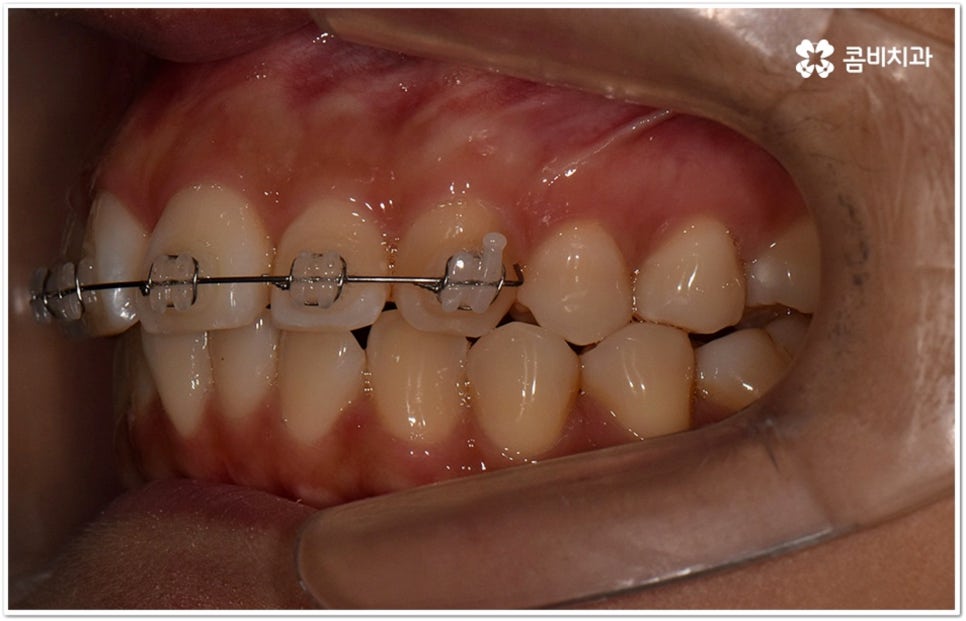

덧니의 원인에는 여러 가지가 있는데 대표적으로는 유치가 너무 일찍 빠져서 영구치가 제대로 자리를 잡지 못했거나 턱뼈의 크기와 치아 크기가 조화를 이루지 못하는 경우 등 공간이 부족한 상황을 생각해 볼 수 있어요. 덧니는 주로 송곳니가 가장 흔하나, 치열이 공간이 부족할 경우 이론적으로는 어떤 치아라도 덧니가 될 수 있어요. 이때 원인과 정도를 꼼꼼하게 파악하여 만약 해당 부위만 부분 교정이 가능하다면 덧니부분교정 치료를 할 수 있는데요. 덧니부분교정 을 이용하면 원하는 부위에만 브라켓을 부착하여 치아 이동을 시키기 때문에 전체 교정에 비해서 간편하며 치료 기간도 6~8개월 정도로 줄어들고 통증도 많이 감소될 수 있습니다. 비용적인 부담도 덜하며 (삐뚤어진 정도나 상태에 따라 다르겠지만) 보통 덧니부분교정 의 경우 비발치 과정으로 진행되기 때문에 환자분들의 입장에서는 덧니부분교정 을 많이 선호하시는 편이라고 할 수 있어요. 상황에 따라 미니스크류, 치간삭제, 악궁확장장치 등 환자에게 맞는 비발치 방법을 이용하여 도움 받을 수 있습니다.

요즘 가장 많이 쓰이는 클리피씨 장치는 이런 면에서 많은 장점을 가지고 있어요. 예전과 다른 자가 결찰 방식을 이용하기 때문에 마찰로 손실되는 교정력이 줄어들어 좀 더 적은 힘으로도 부드럽고 지속적인 치아 이동을 가능하게 하므로, 상황에 따라 다르지만 보통 6개월 정도의 기간 단축 및 이동시 초기에 느낄 수 있는 통증을 덜어준다고 할 수 있는데요. 그밖에도 치아 색상의 브라켓을 이용하여 심미성 또한 뛰어나며 상황에 따라 환자분들에게 맞게 내원 횟수도 줄여줄 수 있다고 하니 숙련된 의료진과 충분하게 상담해 보시고 신중한 선택하시길 권유드리고 있습니다.